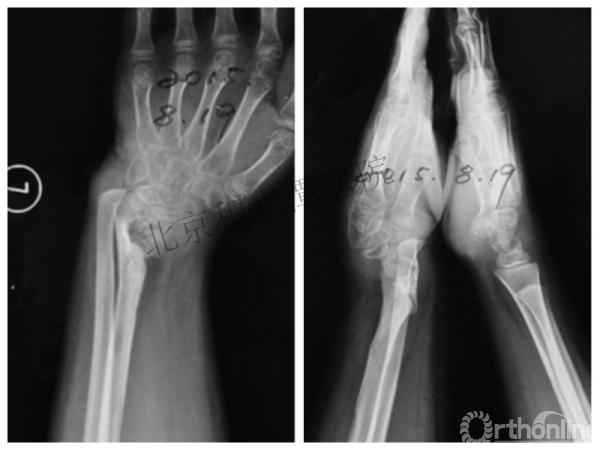

病例分享四

女孩、8岁,桡骨远端骨折

原始损伤

伤后1个月

伤后14个月